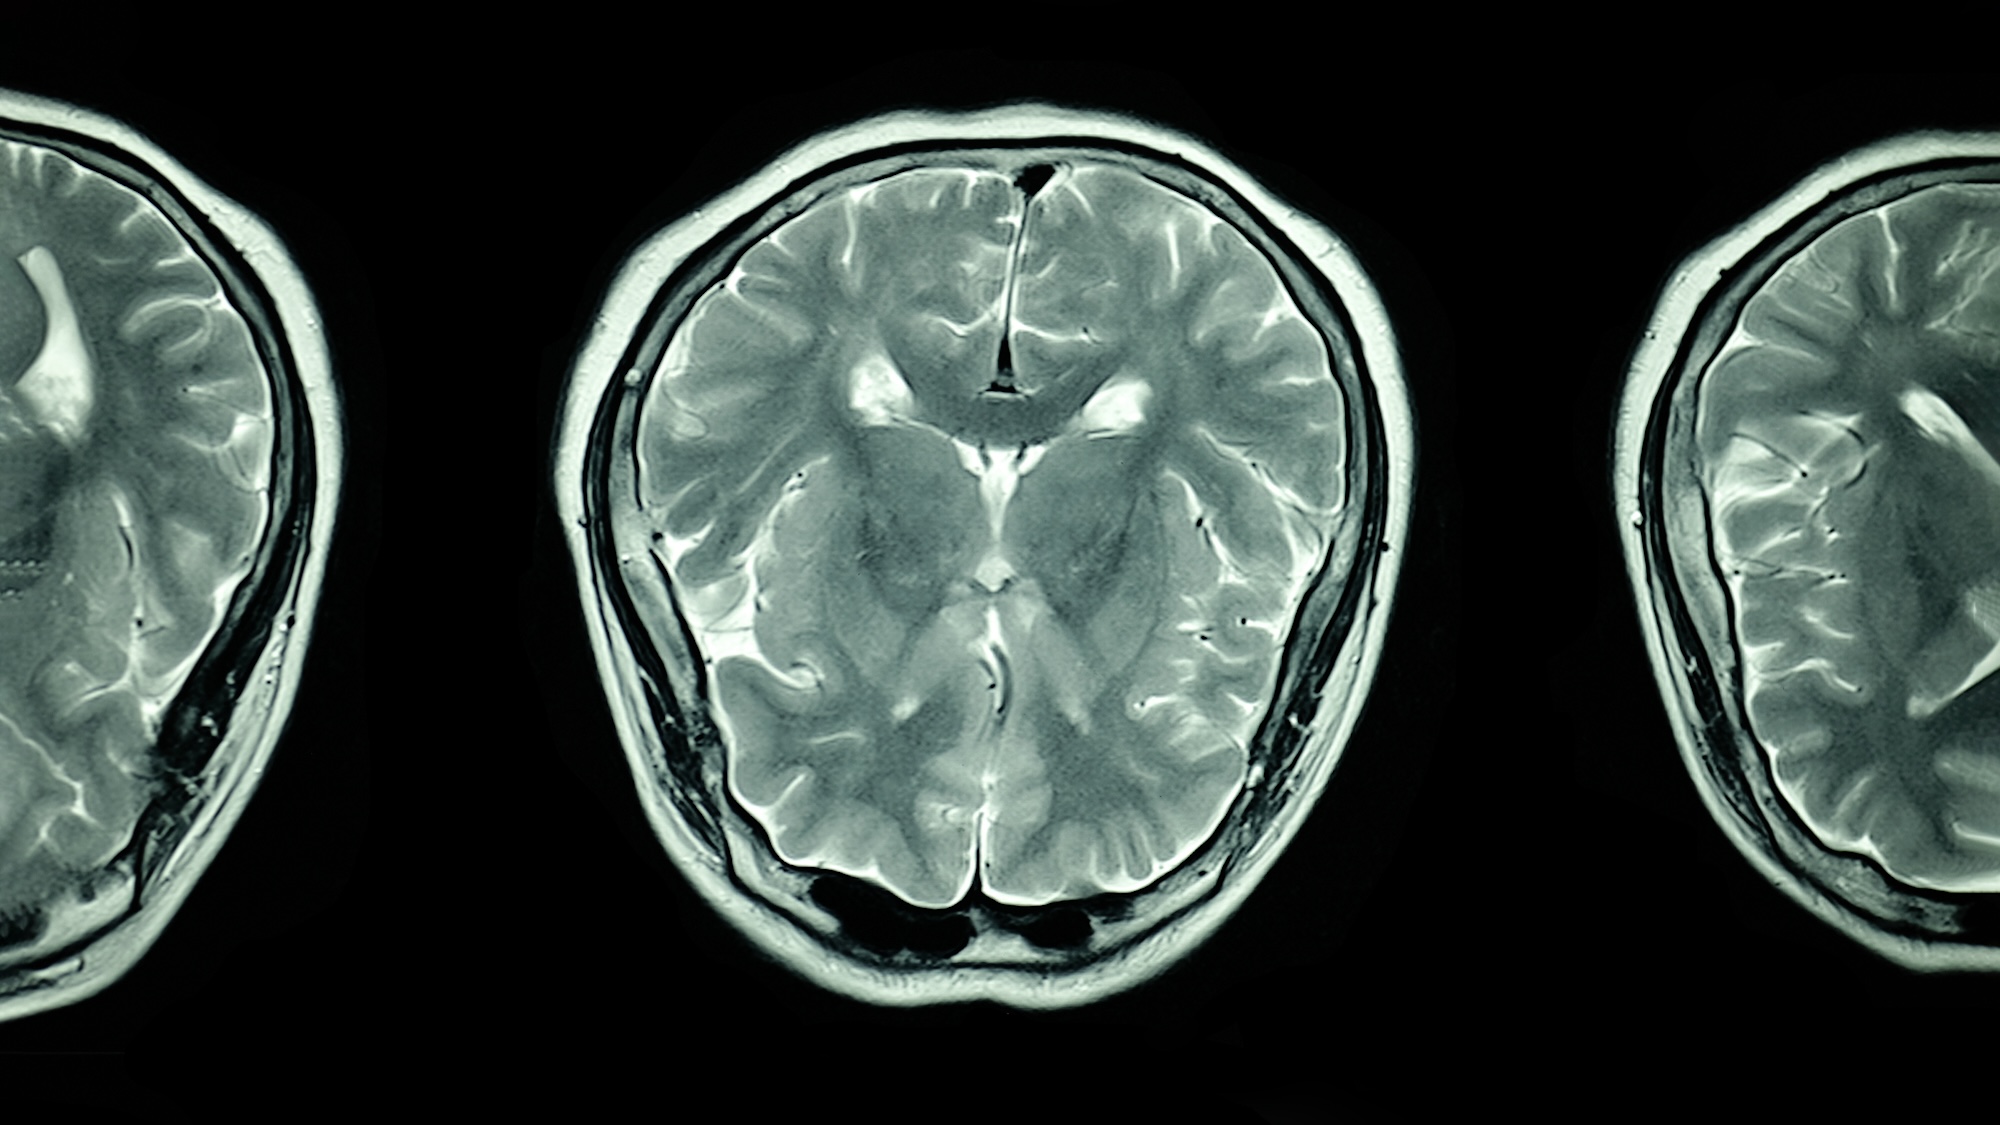

mri scan of the brain

New data suggests languages may share overlapping regions of brain activity. Deposit Photos

The additional data appears to contradict previous neuroscience studies that suggested separate brain regions are activated depending on a given language. In this case, however, much of the area-specific activity overlapped for Spanish and English.

There is also evidence that the patient’s neural activity largely mirrored those of people raised bilingual, despite only learning a second language as an adult. Researchers believe this might imply languages share some neurological features, in which case future implant translation technology could be more generalizable. While the brain implant advancements have so far only been studied in one patient, the team hopes to expand the scope for more participants, as well as experiment using other languages.